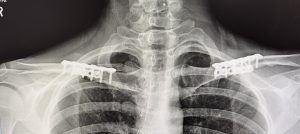

The placement of the incision is directly above the best location to remove the segment of clavicle bone which is at its inner third. This is the thickest part of the clavicle by cross-sectional diameter and is also the most stable being closest to the sternum. The small skin incision is placed, not over the bone, but up above in the supraclavicular fossa which provides for the most favorable scar healing. The segment of bone removed is typically in the range of 2.0 to 3cms per side. Short rigid plate and screw fixation of the shortened clavicle is used for stabilizing the two bone ends. This results in a bideltoid width reduction of 5 to 6 cms which creates a a more narrow and slightly rounded shoulder appearance. This has also been shown to result in uncomplicated bone healing and no adverse effects on shoulder function.

A common postoperative question is whether the plate and screw hardware will ever need to be removed. Usually it does not unless it causes symptoms such as discomfort or visibility. The latter is the most common reason for removal which can be done anytime after 12 months or one year from the original surgery. Hardware removal is not associated with the significant recovery associated with the initial clavicle reduction surgery in terms of arm range of motion restriction.